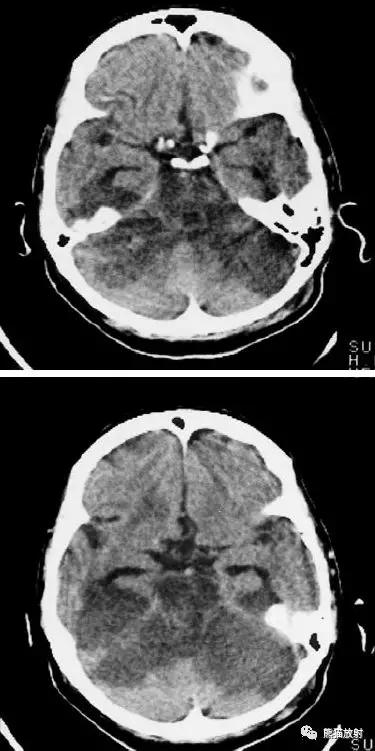

右侧大脑前、中动脉供血区梗死,可见明显占位效应。

右侧大脑前、中、后动脉供血区巨大梗死

分水岭脑梗死(“Watershed” infarcts):右侧大脑前中动脉及中后动脉供血区之间梗死灶。

分水岭脑梗死:左侧深部和浅部大脑中动脉供血区之间梗死灶。